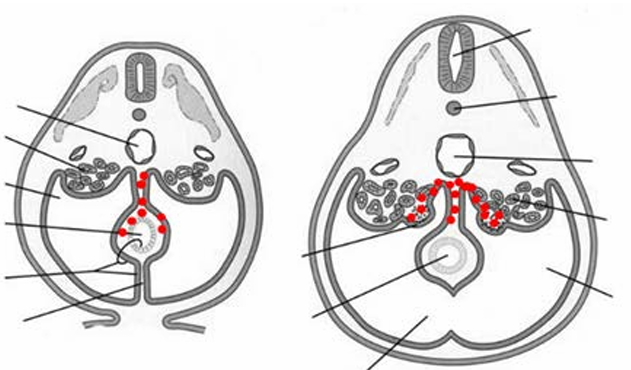

Welke zenuwen zijn betrokken bij de erectie en welke zenuwen zijn betrokken bij de ejaculatie?

A

erectie:

- parasympatische zenuwstelsel (S2-S4): nn. splanchnici pelvici: zorgt voor vasodilatatie. De vezels hiervan komen in de n. cavernosus die dus zorgt voor de vasodilatatie.

- n. pudendus (somatisch): stuurt de m. ischiocavernosus en m. bulbospongiosus aan.

ejaculatie:

- sympathische zenuwstelsel (Th11-L2): nn. splanchnici en plexus hypogastricus inferior: zorgen voor de emissie van de sperma door contractie van de zaadleiders, prostaat en zaadblaasjes. Zorgt ook voor het sluiten van de blaashals door de m. sphincter urethrae interna.

- n. pudendus: ritmische contactie van de bekkenbodemsphincter, en de externe urethrale sphincter wat leidt tot de daadwerkelijke ejaculatie.

- De vezels van het sympathische zenuwsstelsel (uit de plexus hypogastricus) zitten ook in de n. cavernosus en zorgen voor het beëindigen van de erectie.

Q

Hoe werkt de erectie?

Tactiele stimulatie van de genitalia zorgt voor reflexogene stimulatie in het sacrale erectie centrum (S2-S4) in het ruggenmerg. Het thoracolumbale erectie centrum (T11-L2) zorgt voor vasodilatatie, een verhoogde bloed-flow door de penis en een erectie. Daarnaast hebben allerlei psychogene stimuli ook invloed op de erectie. Parasympatische stimulatie zorgt voor relaxatie van glad spierweefsel. Hierdoor neemt de bloedstroom in het zwellichaam toe, en daardoor wordt de veneuze afvoer dichtgedrukt.

Bij de seksuele responscyclus van de man zijn zowel de hypogastrische (sympatische) en bekken (parasympatische) zenuwen betrokken. De nervus hypogastricus, de sympatische zenuw, zorgt voor detumescentie van de penis (het verdwijnen van de erectie).